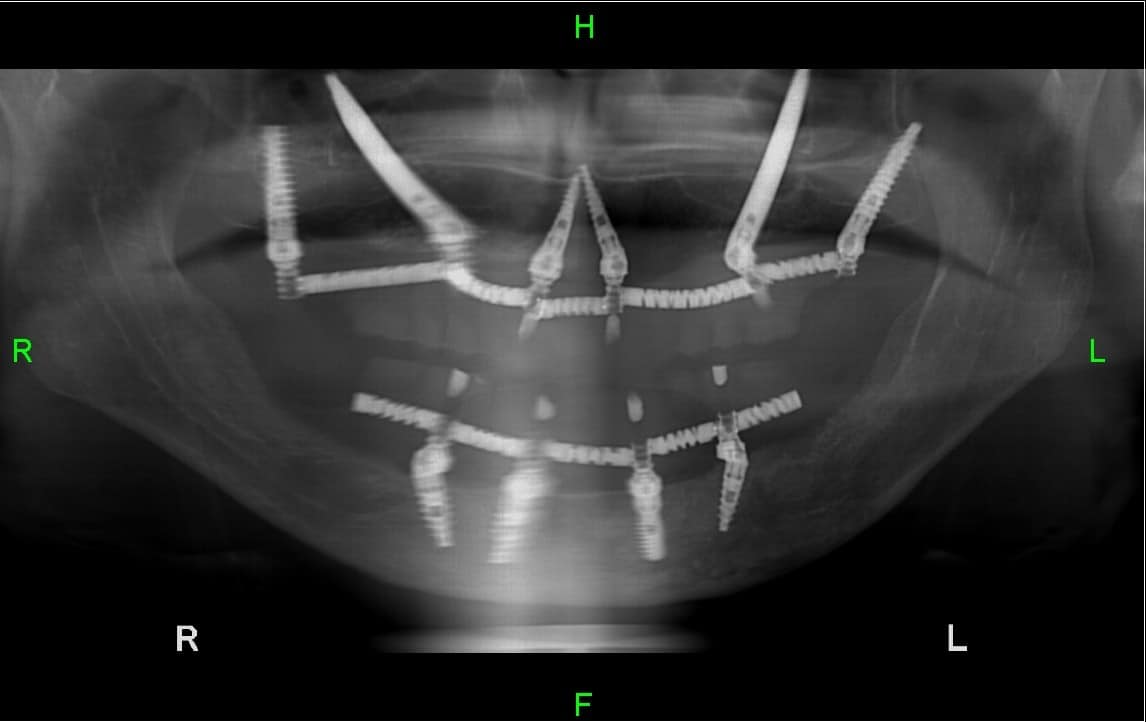

In this x-ray below presents what the 4 implants that have been inserted into the patient’s upper and lower jaws look like.

Dental implants on 4 implants - All on 4